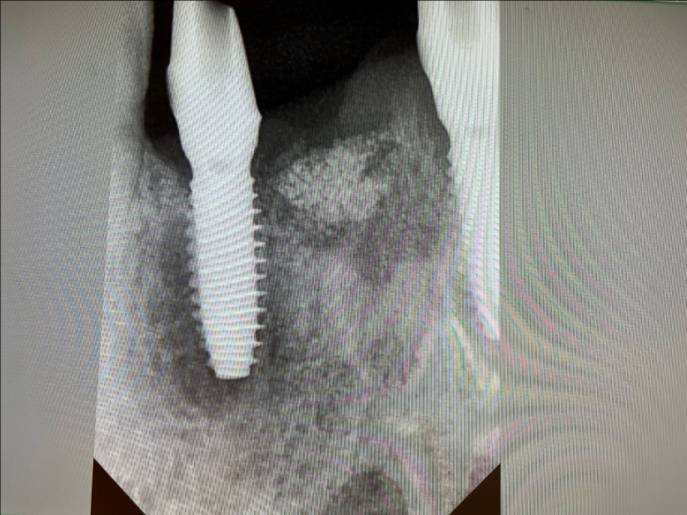

물론 강한 골질을 만나 식립토크가 크게 걸릴 수 있고 fixture 윙의 변형이나 fixture 위치설정이 어려울 수 있다.

이 경우 식립 드릴링 시 골밀도를 꼭 체크해야 한다. 그렇다고 단단한 골질을 만나서 fixture가 변형이 생길까 미리 걱정할 필요가 없다.

Bright implant는 재질이 cold work grade 4로 제작되어 grade 5 수준의 강도를 가지고 있다. Bright implant는 높은 초기 고정력이 있어 즉시 및 조기 부하도 가능하다. 참고로 헤드가 작아서 토크렌치를 돌릴때 작은 헤드 부분이 덜 걸려 미끄러질 수가 있다. 꽉 누르고 토크렌치를 돌리는 것이 좋다.

Bright implant tissue Level은 Dentium Simple Line과 비슷하며 tissue level 상부 돌출부는 6각으로 되어 있다. 베벨까지 내려가서 측방압에 강하고 실링효과가 높아 leakage 없고 따라 bone loss의 염려가 없다.